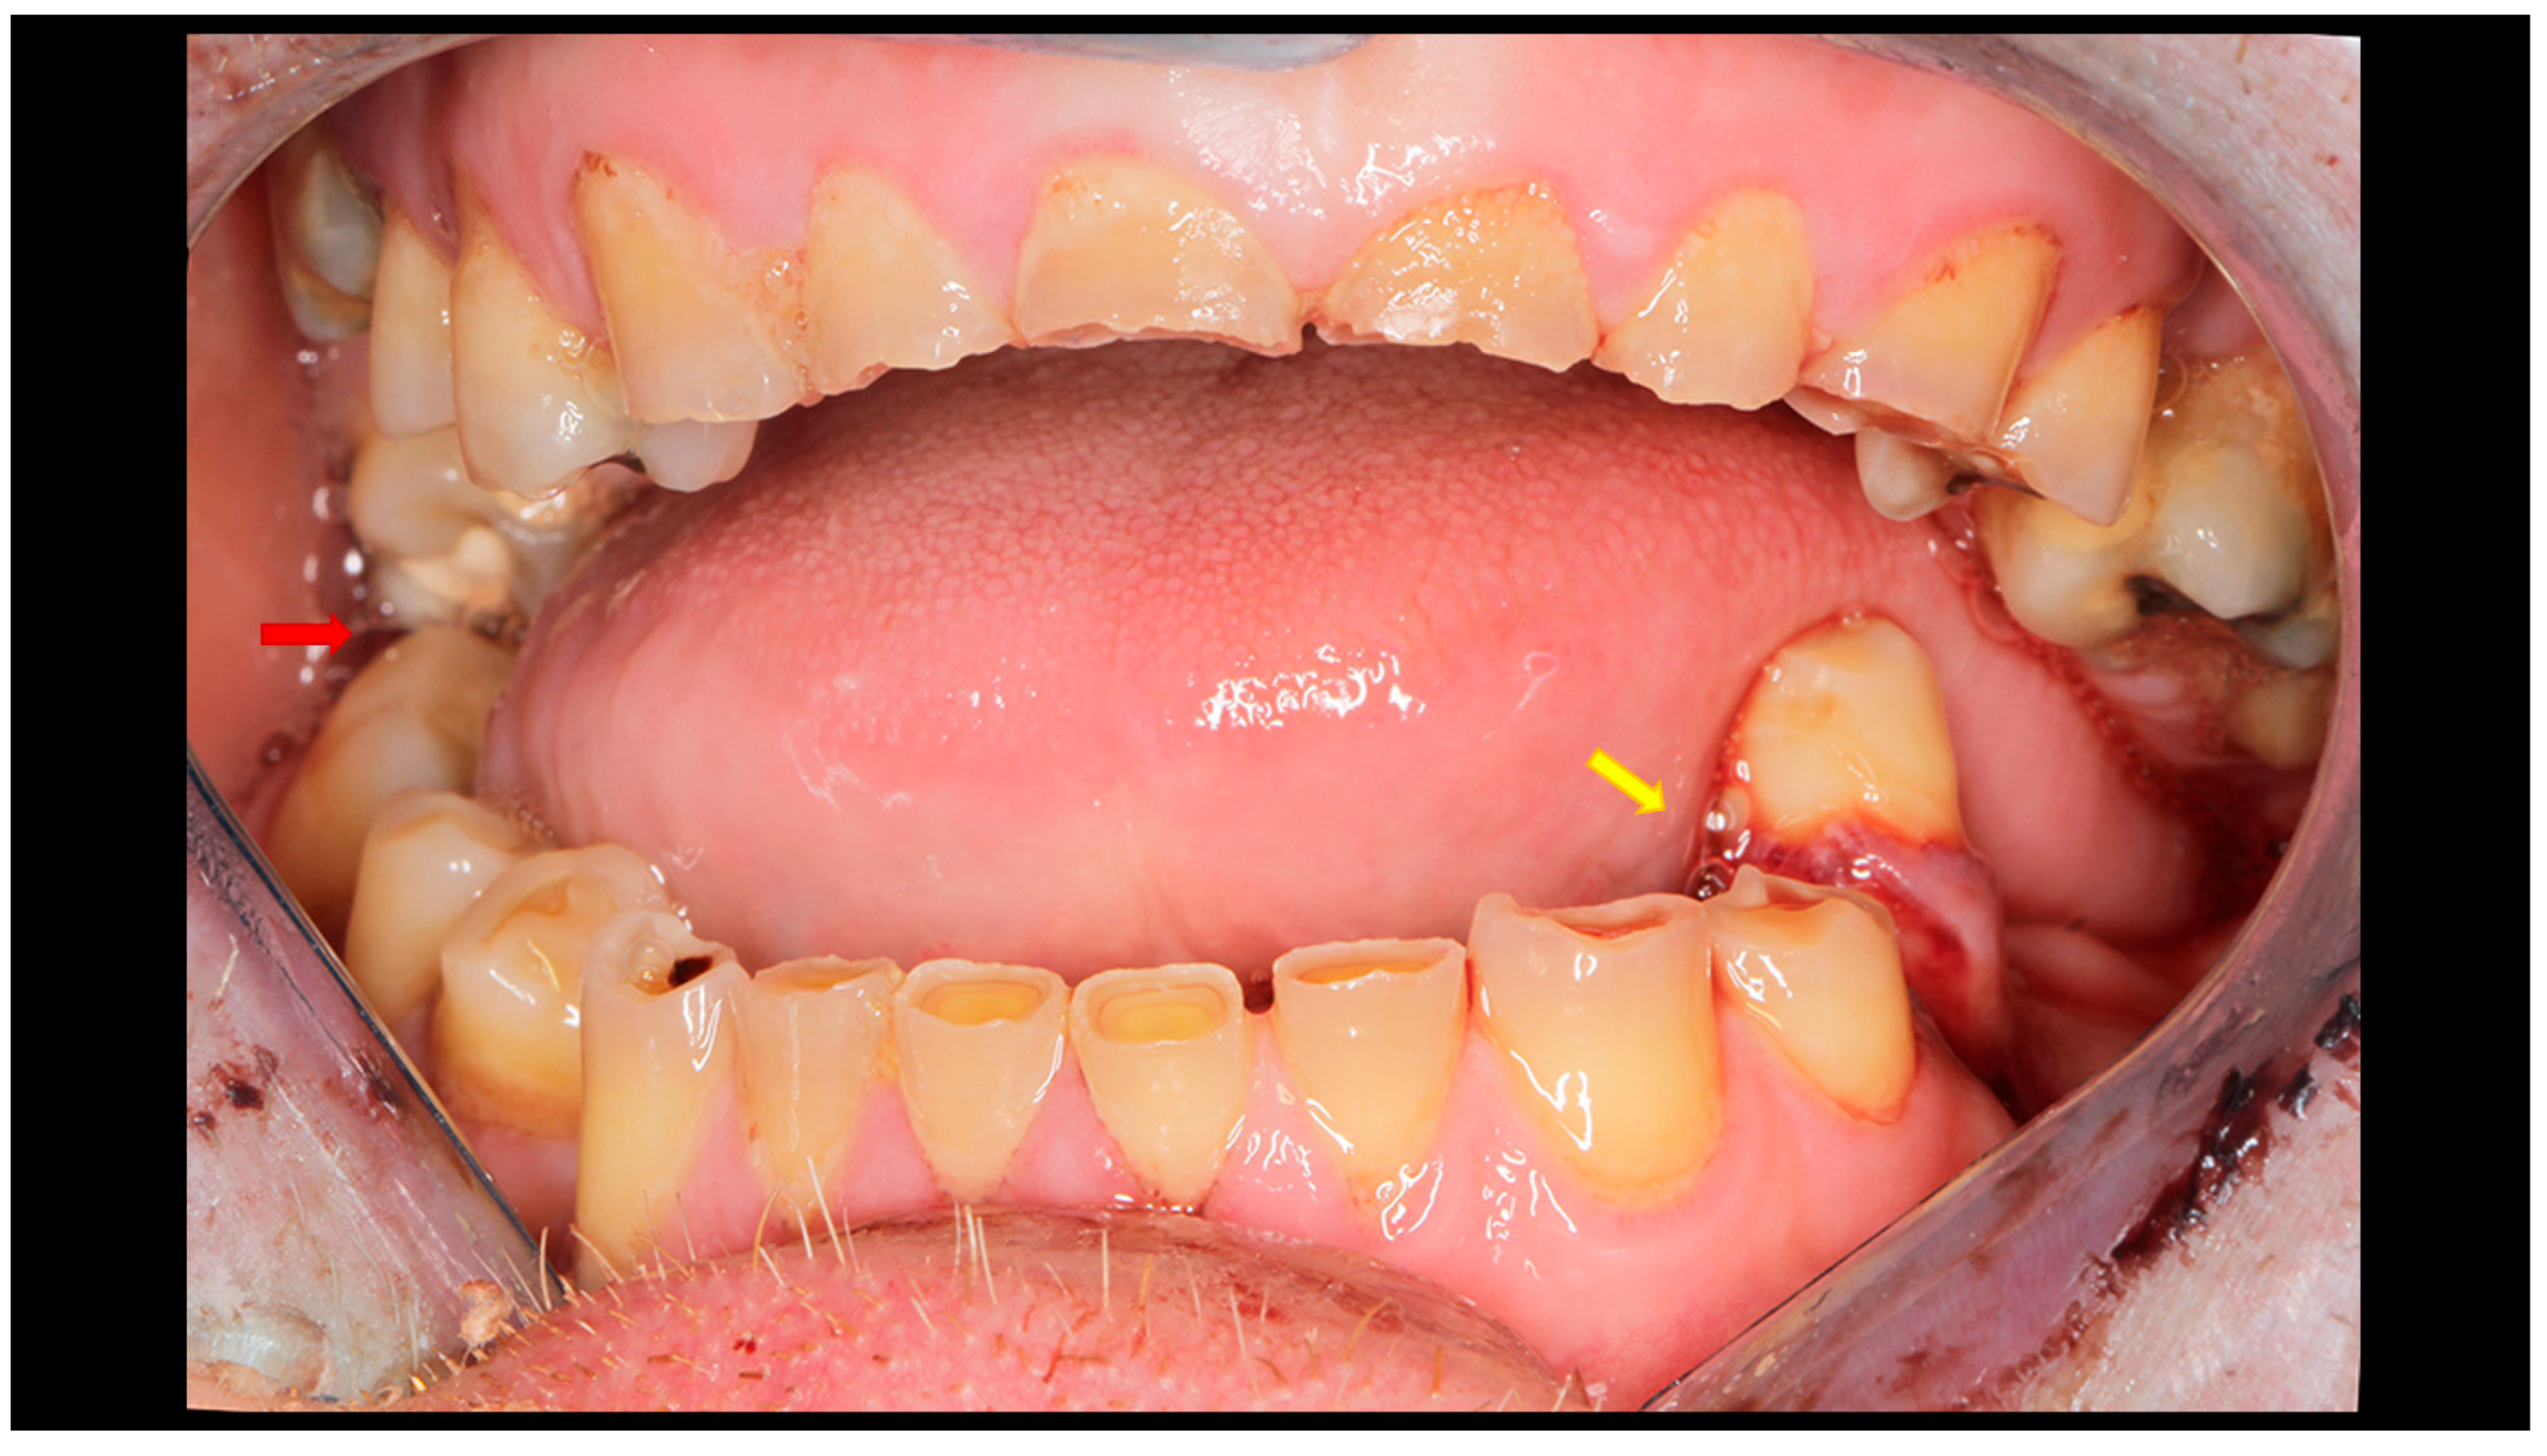

Figure 2.

Post-traumatic malocclusion. The mandible is divided into three pathological parts. The proximal fragments are displaced upward, while the distal fragment (the middle one) is displaced downward. This results in a completely open bite with dental contact only on the last teeth in the dental arch (red arrow). Please also note the break in the occlusal line resulting from an open fracture of the mandible on the left side (yellow arrow).